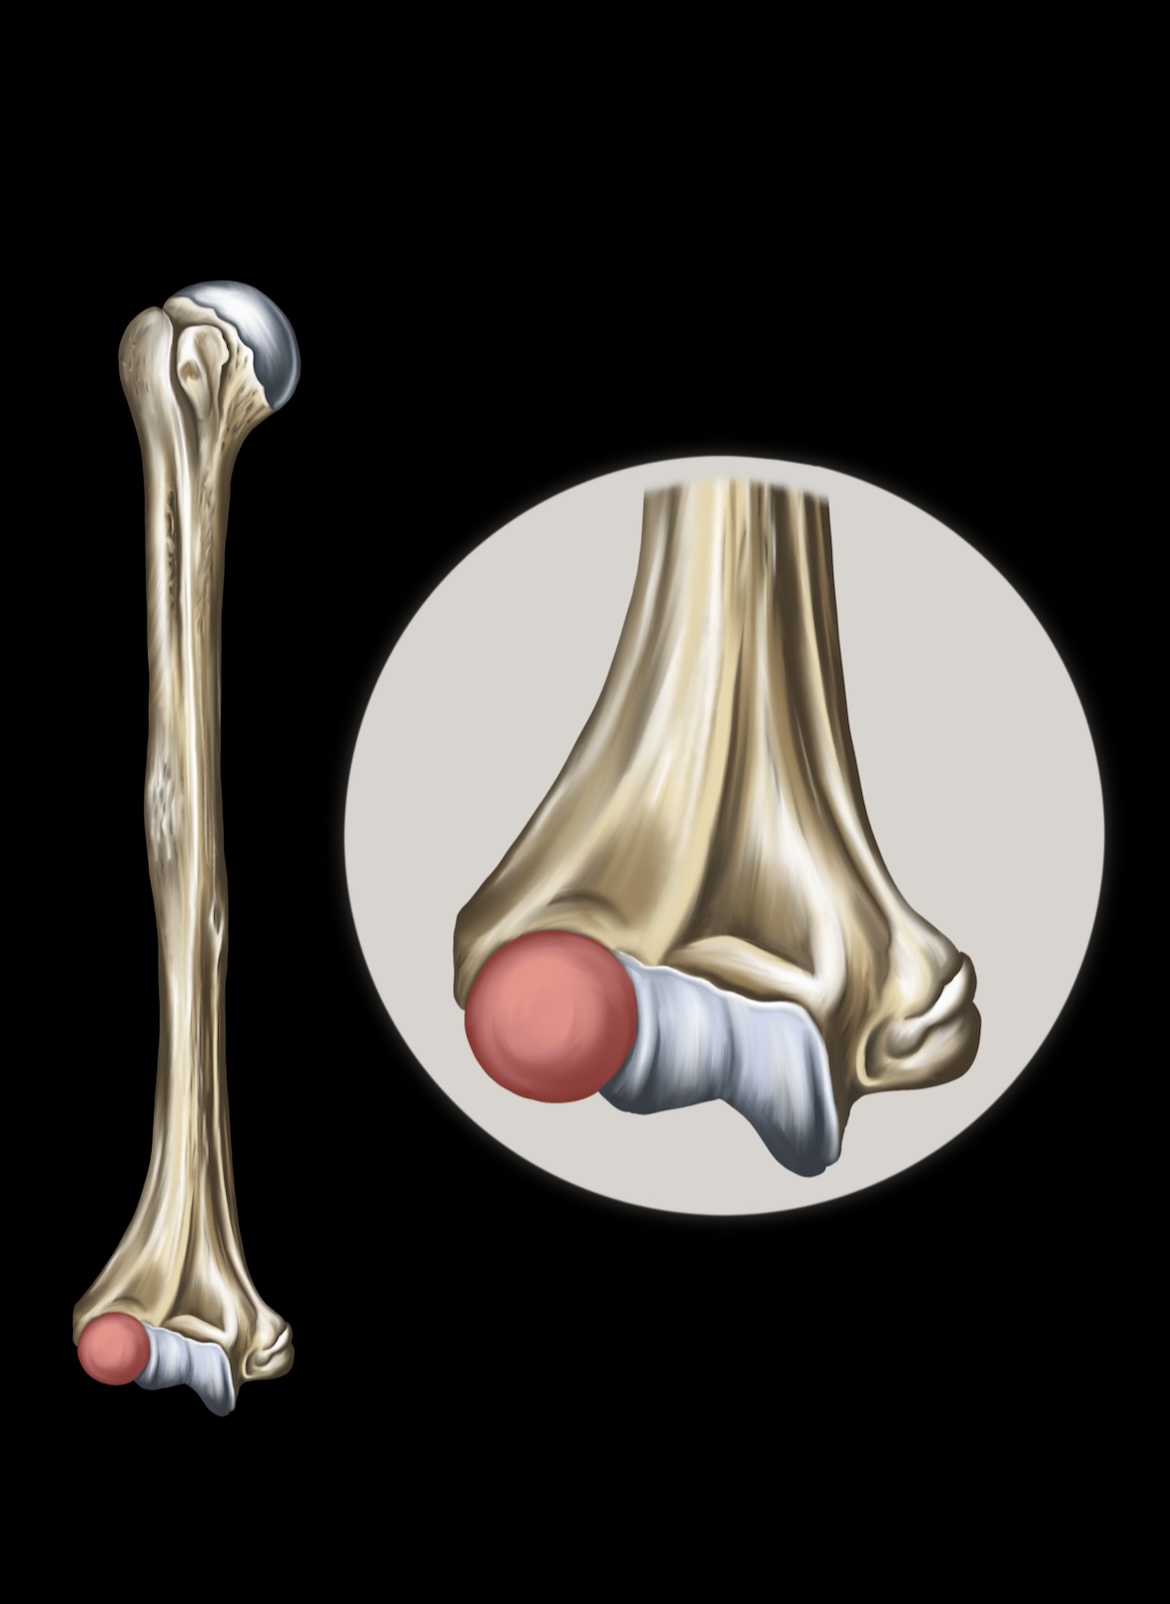

Humerus

Lateral Epicondyles of the Humerus

Medial Epicondyles of the Humerus

Ulna

Olecranon

Trochlear Notch